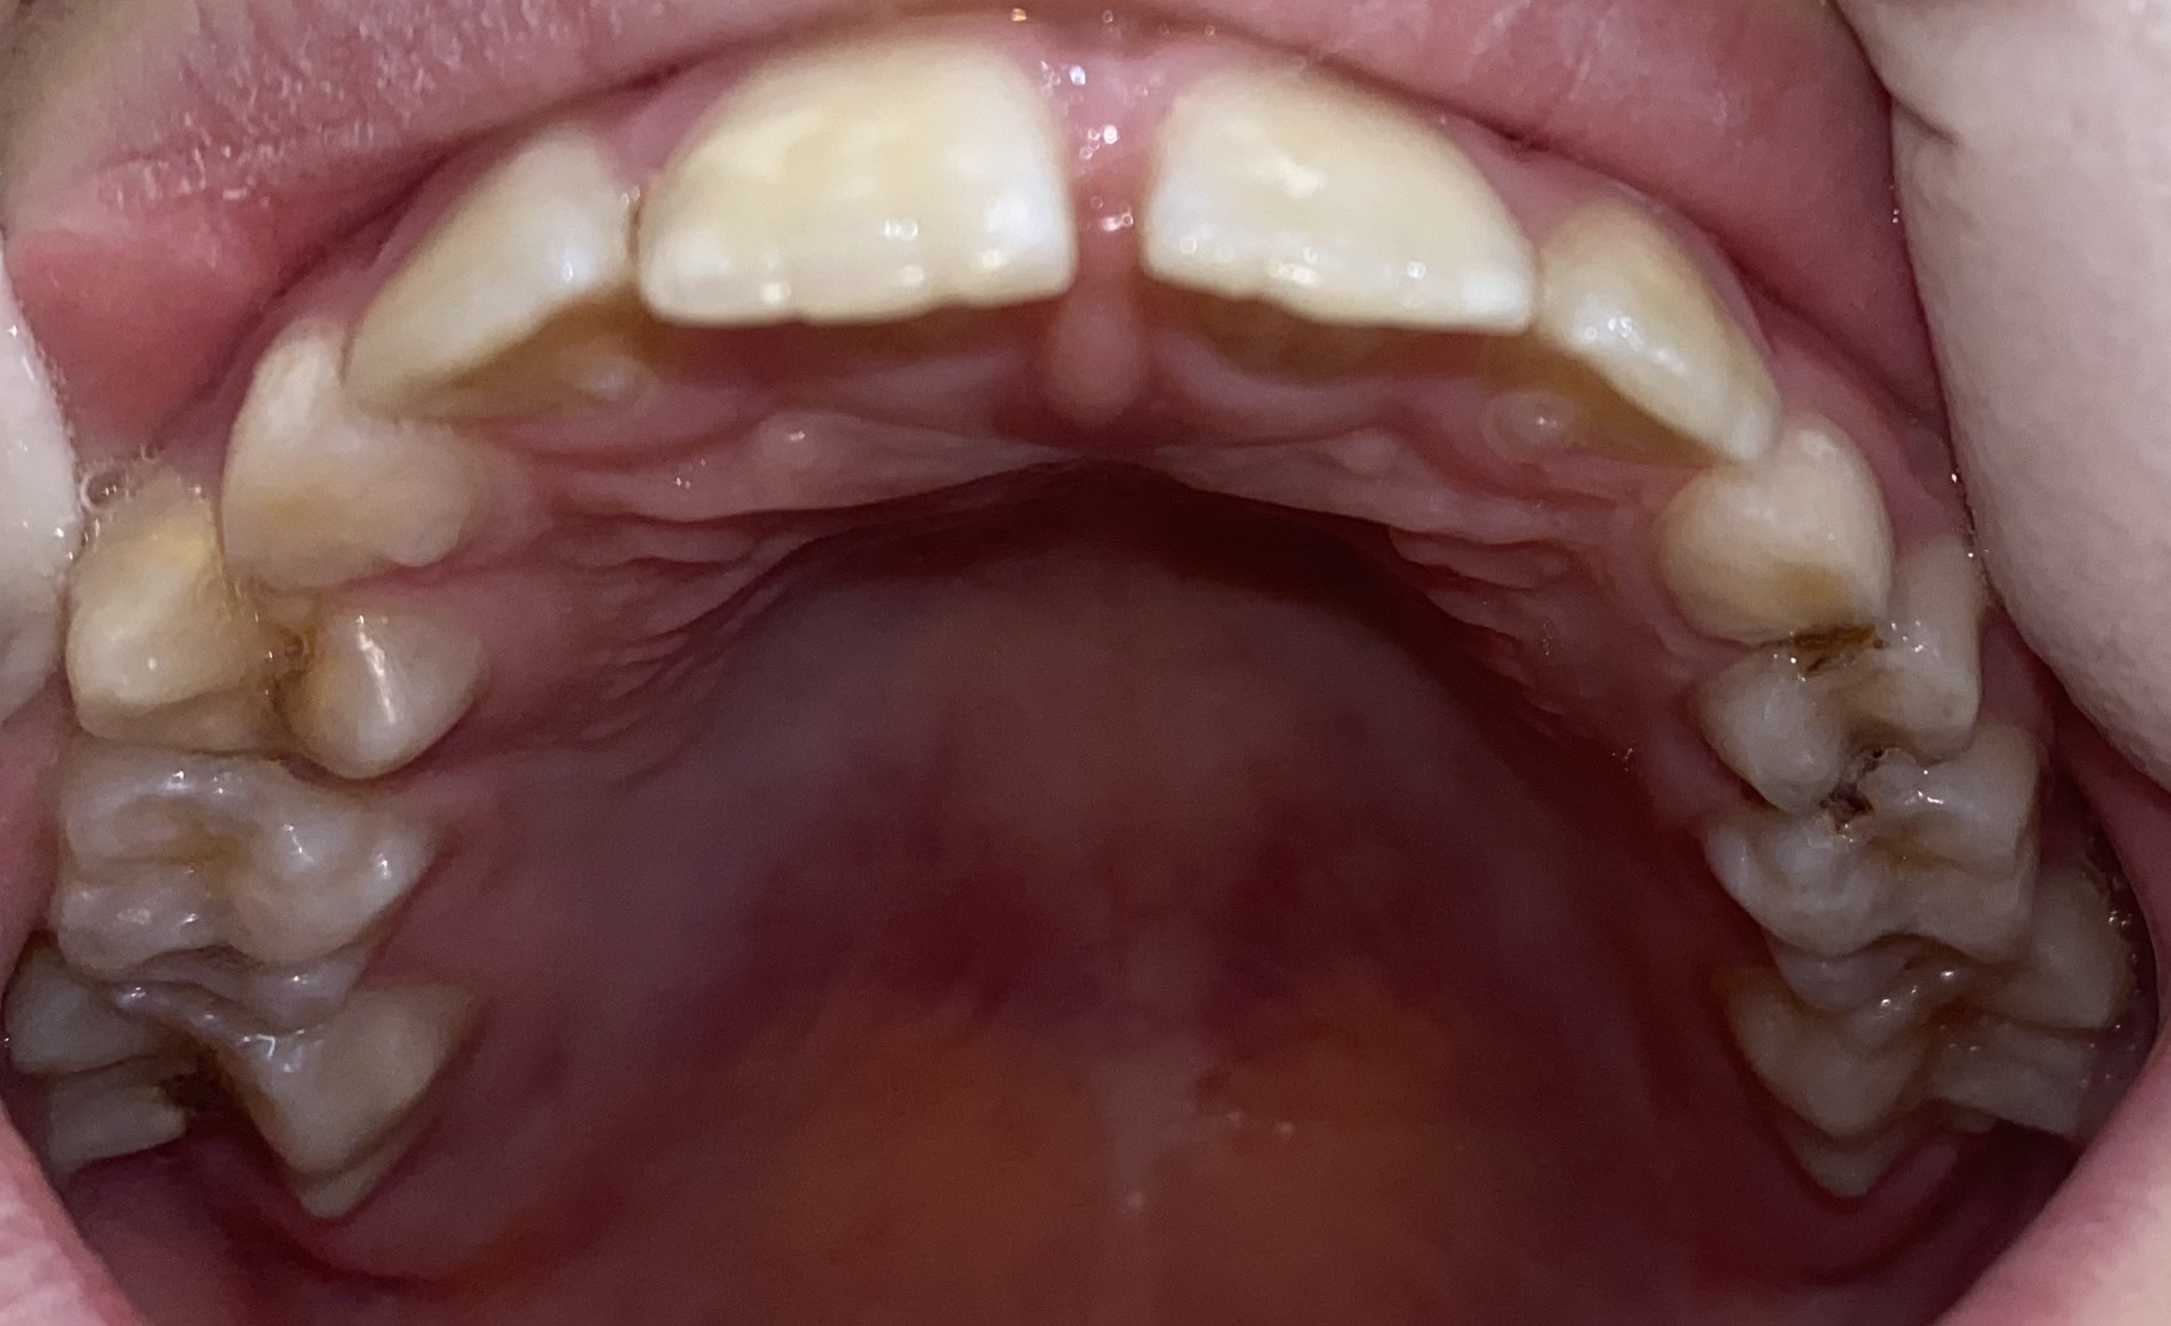

![]() |

| Upper | Front | Lower |

To enable research of computer vision methods in dentistry we have collected and annotated the TriDental dataset consisting of RGB images of oral cavities. The images were collected by medical professionals. The dataset contains images of oral cavities of 1000 individuals. Each individual’s oral cavity was photographed from three distinct views as shown in Fig. 1 resulting in 3000 RGB images.

To annotate the data we have created an online annotation tool that could be used by annotators. Each sequence of three views could be loaded at once. The annotators then provide keypoints for each tooth in each view. Since keypoint location on a tooth is not well-defined the annotators were instructed to choose keypoint locations corresponding to the centers of teeth. Annotated keypoints can be seen in Fig. 2.